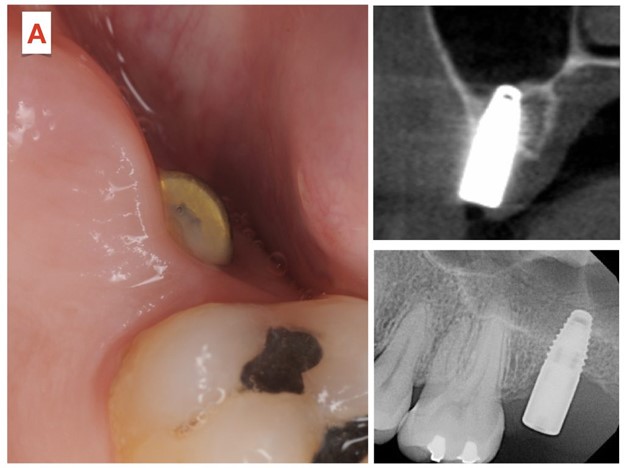

در فک بالا، ایمپلنت های دندانی در نزدیکی سینوس فک بالا – که بالای دندان های عقب فک بالا قرار دارد – قرار می گیرند. ایمپلنت های دندانی که به درستی قرار نگرفته باشند، می توانند به حفره سینوسی آسیب برساند و منجر به مشکلات سینوسی مانند سینوزیت یا عفونت های مزمن سینوسی شوند که با درد همراه هستند. علاوه بر این، ایمپلنت دندانی که خیلی بالا و در قسمت جلوی فک قرار گرفته باشد، می تواند منجر به سوراخ شدن بینی شود، جایی که ایمپلنت دندانی از کف بینی عبور کرده و از داخل حفره بینی بیرون می زند. این عوارض می توانند باعث گرفتگی سینوس و بینی، درد، عفونت و حتی نیاز به برداشتن ایمپلنت دندانی شوند. از تجربه، مهارت ها و توانایی های جراح ایمپلنت دندان خود مطمئن شوید. برای جلوگیری از این نوع عوارض، به دنبال یک متخصص ایمپلنت دندان دارای مجوز باشید.